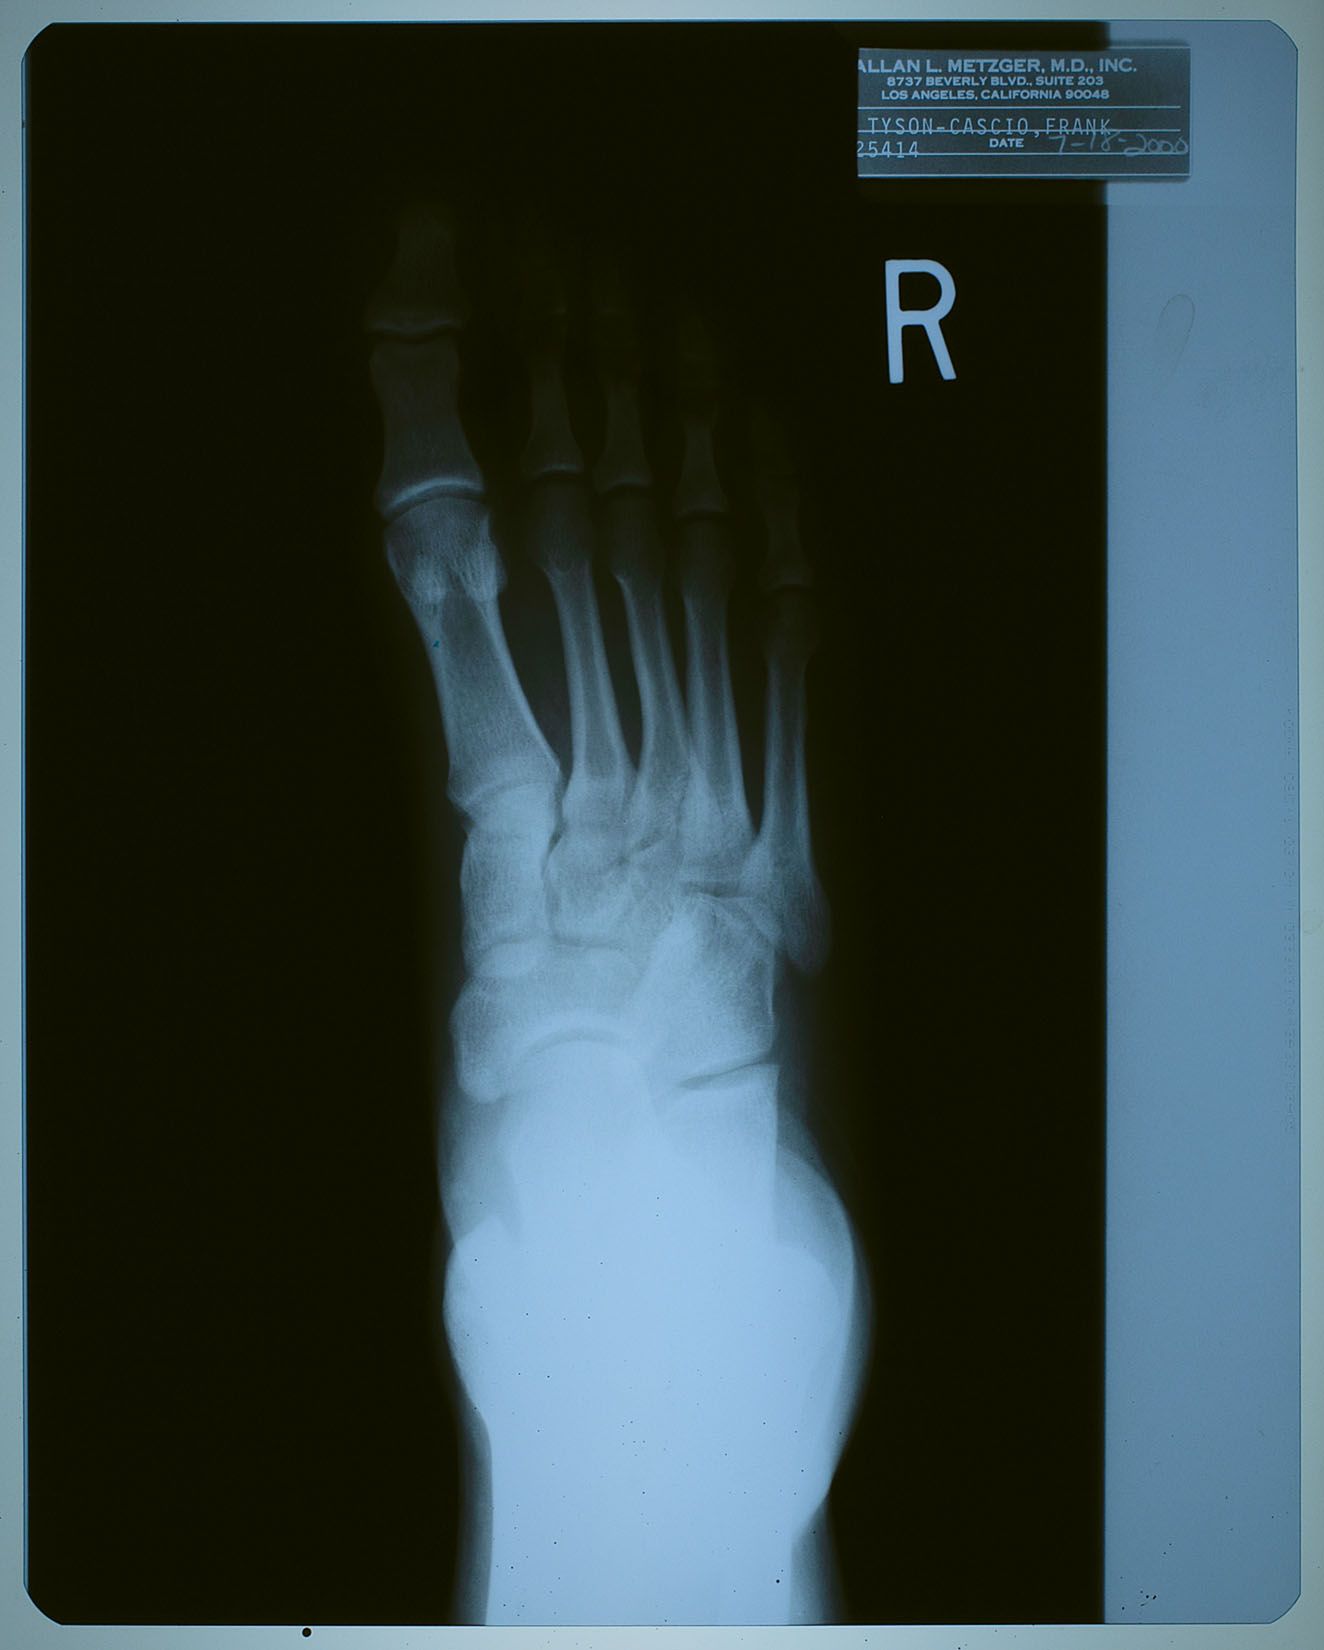

2000年7月18日、ネバーランドで子供たちと遊んでいて

怪我をした時に撮ったX線写真。

名前が 「タイソン-カシオ,フランク」 になっているけども、

カシオ本を読んだ御仁はお判りでしょう。

"タイソン" というのは、前年からマイケルの代理人を務めるようになった

フランク・カシオ君の仕事上での通名。

診療所などでは、マイケルがプライバシー面からフランク君の名を使う事もあったそう。